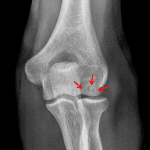

- Osteochondral lesion in the capitellum measuring 12 x 8 mm

- Otherwise no acute fracture

- Elbow joint effusion

- Osteochondral lesion (OCL)

Osteochondral lesion in the capitellum measuring 12 x 8 mm. No displaced osseous fragment or loose joint body identified. Consider MRI for further assessment.

Elbow joint effusion is present. Although no acute fracture is identified, this raises the possibility of an occult nondisplaced (e.g. radial head) fracture.

No joint malalignment.

Joint spaces are maintained.